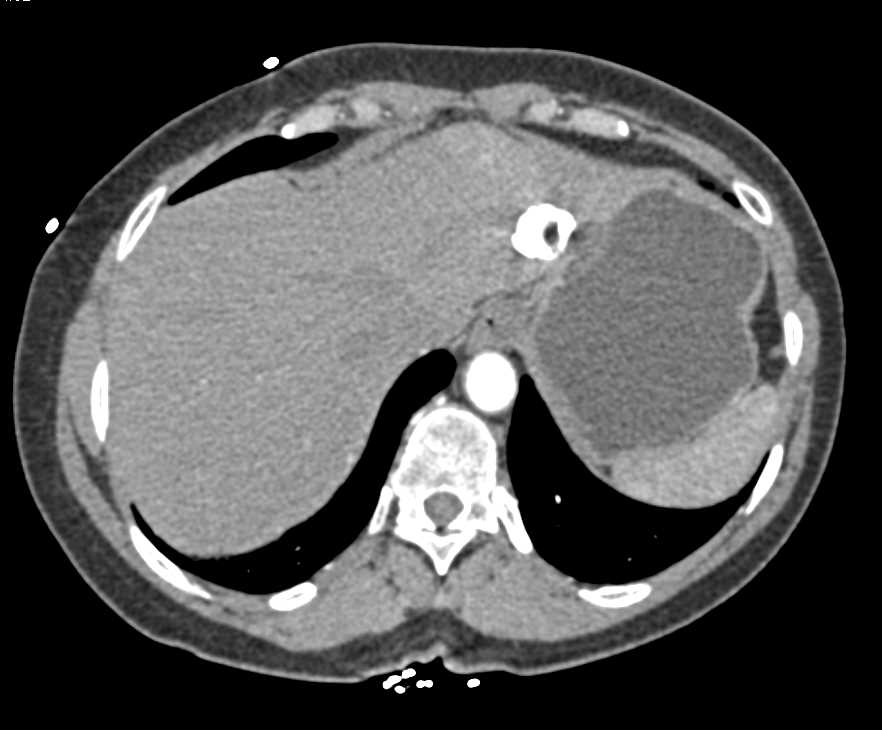

Neuroendocrine Tumor in the Body of the Pancreas with Liver Metastases